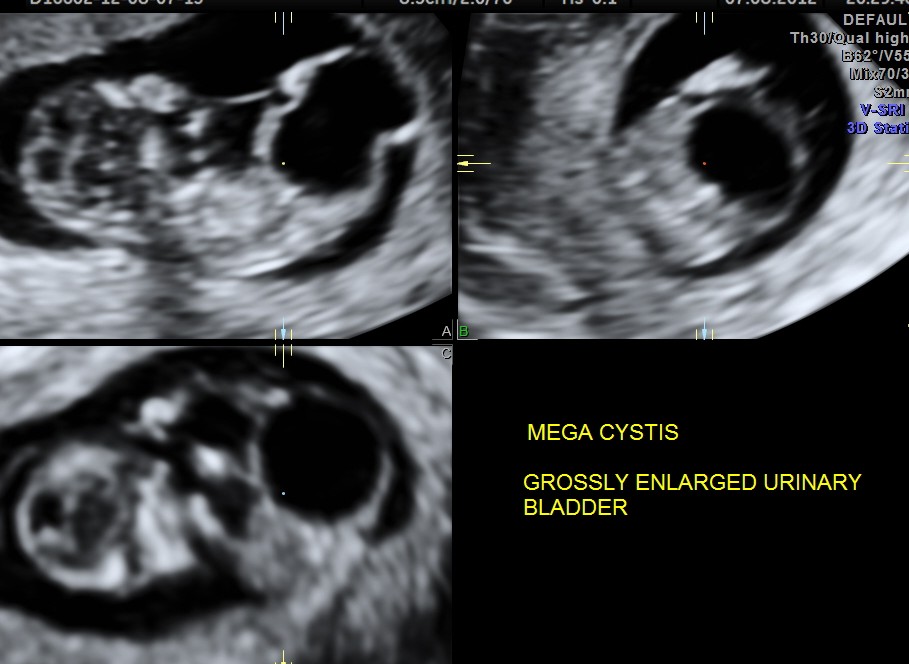

This was a 19 year old primi with history of consanguinity.The scan was done in the first trimester.

A large cystic mass was made out in the lower abdomen.

Will show an enlarged bladder